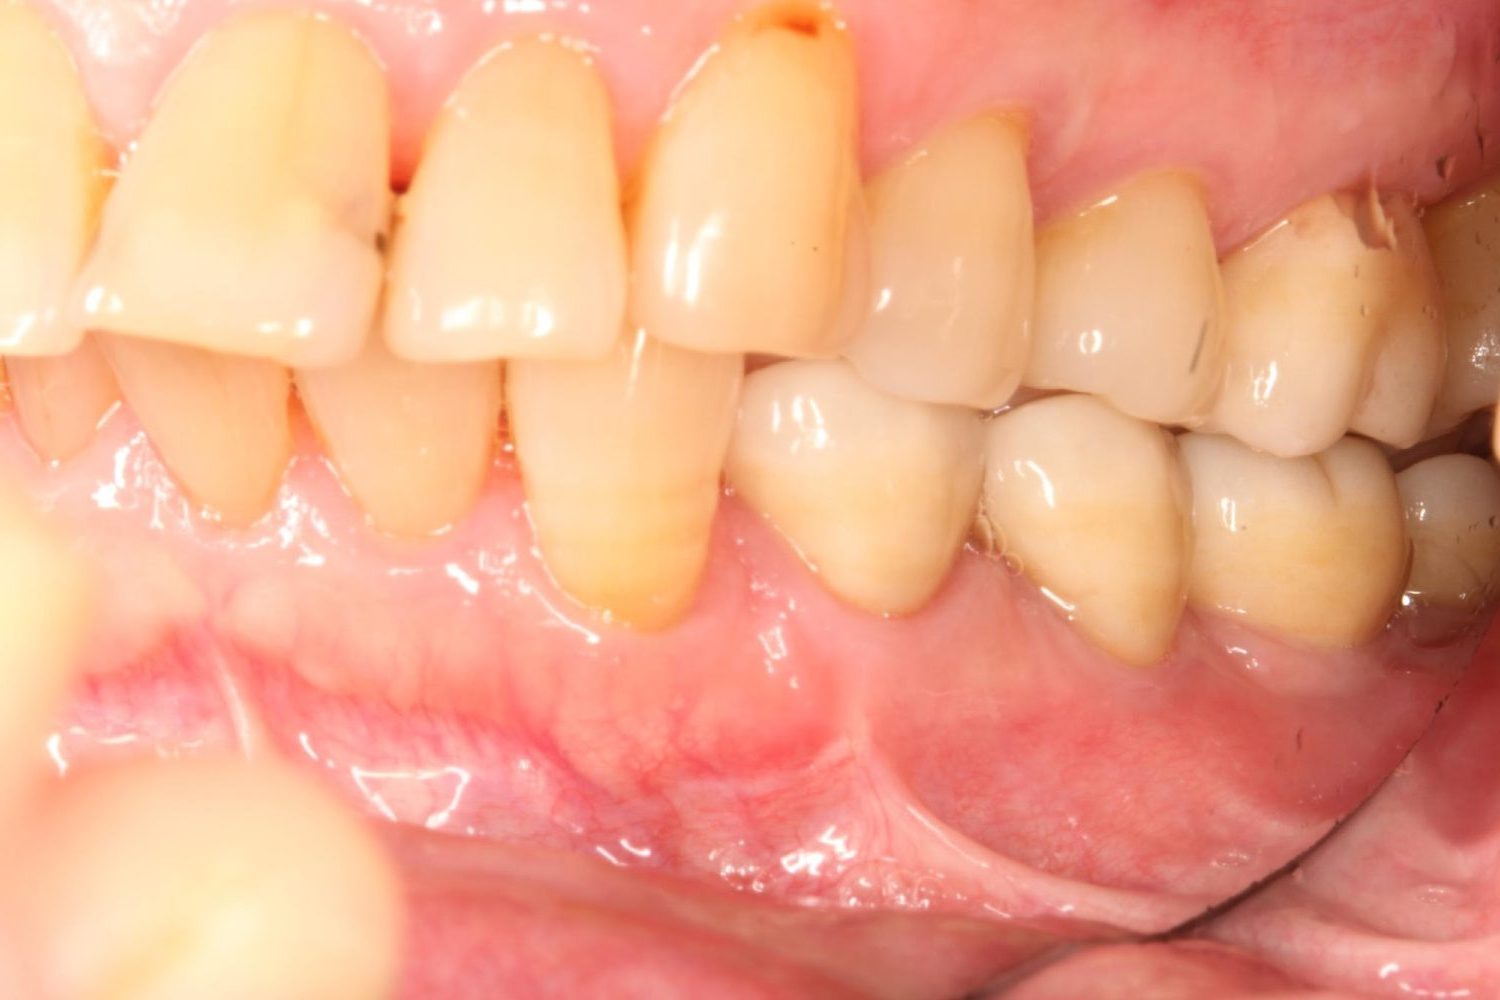

インプラント治療の症例紹介⑤

Before

After

主訴

歯肉腫脹、咬めるようにしたい

治療内容

重度歯周病により全ての残存歯保存不可能な状態。上下顎ボーンアンカードブリッジによる咬合再構成。

治療費

12,621,400円(税込)

治療期間

22ヶ月

通院回数

28回

想定されたリスク

※上部構造の形態が複雑になるため清掃が難しくなる、インプラント周囲炎の恐れがありました。

上顎8本下顎7本のインプラント体埋入によるボーンアンカードブリッジ。